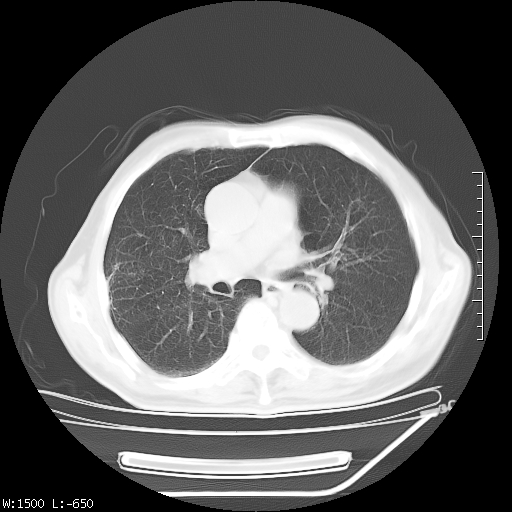

标题: CT23994:男、72、咳嗽、气短两月余,近来消瘦。 [打印本页]

标题: CT23994:男、72、咳嗽、气短两月余,近来消瘦。

tb可能性大(双肺均可见片状密度增高灶,其内可见低密度空洞)。

右上肺大片状密度增高影,与胸膜关系密切,内见低密度透亮影,胸膜下可见三角形不张影,左下肺沿支气管走形结节影,纵膈内淋巴结显示。考虑结核并疤痕性不张可能性大,建议穿刺活检,排除肺泡癌。